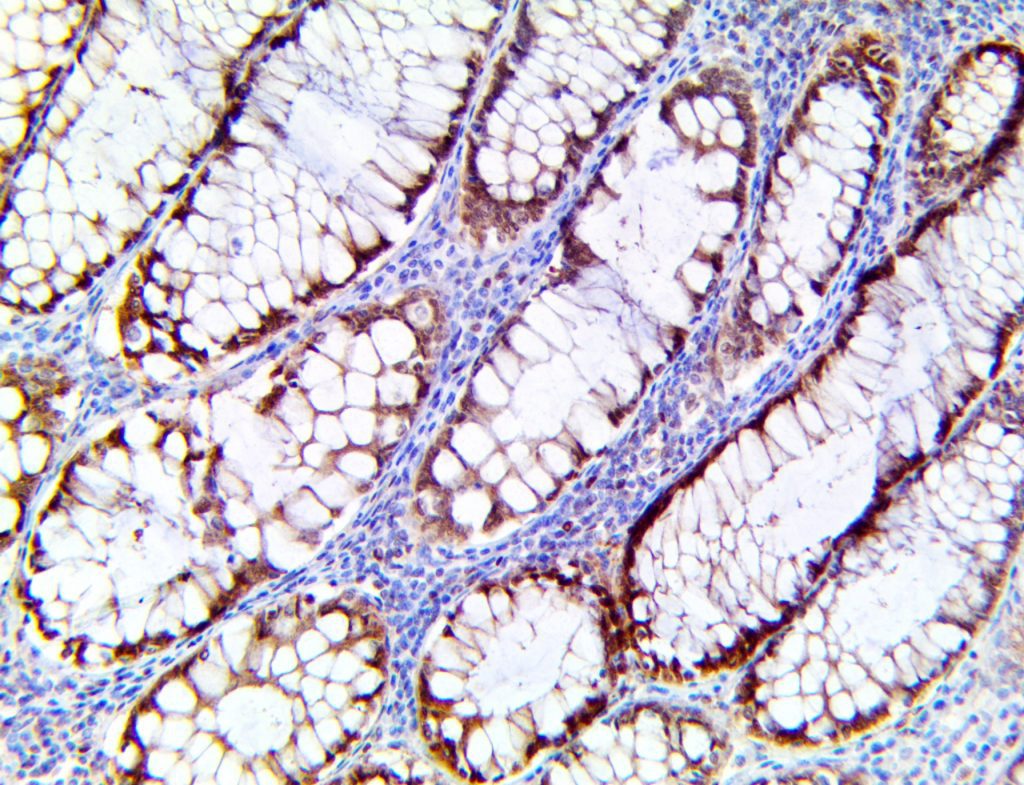

This activation induces inflammatory monocytes to highly express IL-6, starting a localized and then systemic cascade effect that results in hyperproduction of IL-6, which accelerates the inflammatory process. Because IL-6 also increases vascular permeability, excessive levels cause blood vessels to become very leaky. This, along with clotting factors released from vascular endothelial cells, stimulates the coagulation cascade, resulting in microthrombosis (tiny clots), which leads to ischemia and tissue death of the kidney, intestines, heart, liver, brain and extremities.